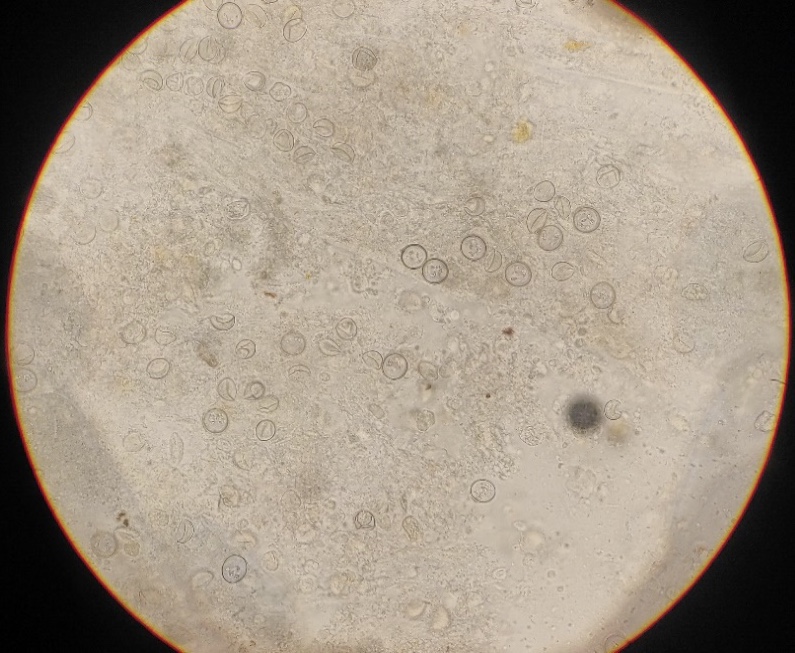

Sono protozoi, parassiti intracellulari estremamente speci-specifici che nei polli appartengono principalalmente al genere Eimeria (o più raramente Cryptosporidium) e che contano diverse specie tra le loro fila.

–Eimeria acervulina: la più comune in allevamento, è principalmente situata nell’intestino tenue (piccolo intestino), la sua oociste è medio-piccola e la sua patogenicità non è particolarmente spinta ma dipende dalla quantità di oocisti ingerite. Un infezione massiccia può portare a cali di crescita, lesioni intestinali biancastre a placche e in alcuni casi morte del soggetto.

–Eimeria brunetti: rappresenta un 5-15% delle coccidiosi in allevamento, sita nell’ultima parte del tenue e nella totalita del grosso intestino (cechi esclusi) ha oocisti poco più grandi di acervulina e da lesioni più gravi, con diarrea emorragica e in casi di alta infestazione mortalità tra il 10 e il 30%.

-Eimeria maxima: il coccide tra quelli che tratteremo di dimensioni maggiori, sita nella porzione media del tenue e da feci ricche di muco arancio/giallo, da cali di crescita ma raramente porta a morte i soggetti.

-Eimeria mitis: sita principalmente nell’ultimo tratto del tenue (dopo diverticolo di Meckel), ha oocisti molto piccole e spesso non presenta lesioni o sintomi evidenti.

–Eimeria necatrix: specie conosciutissima per le palesi lesioni e la forte patogenicità, la posizione è simile a quella di E. maxima ma riproduce più lentamente e spesso i danni sono nei giovani adulti e non nei pulcinotti. Si evidenzia un intestino con parete raddoppiata in diametro con sangue e muco nel lume. Le oocisti si trovano solo nei ciechi, in quanto gli schizonti di 2° generazione migrano li per la fase sessuata. la mortalità può andare dal 25 al 100% in casi estremi.

-Eimeria tenella: coccide più noto per la sua gravità, si localizza nei ciechi e causa diarree emorragiche in quanto si moltiplica coinvolgendo strati profondi della mucosa, gli animali si presentano pallidi, abbattuti e possono andare incontro a morte.